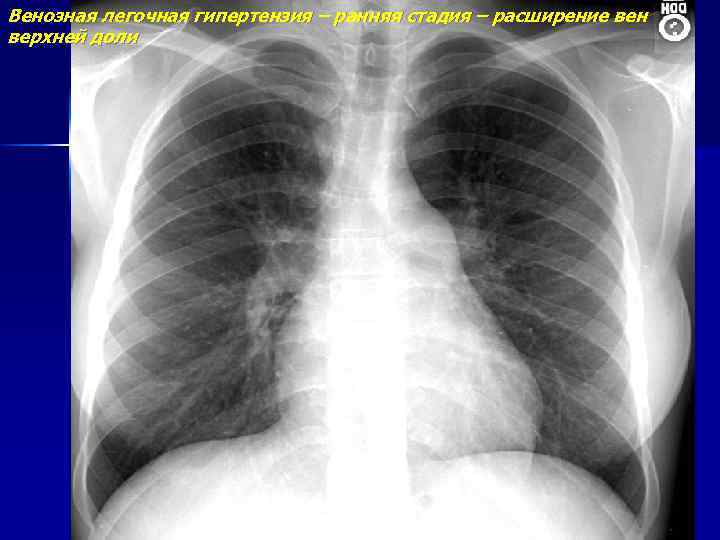

Венозная легочная гипертензия – ранняя стадия – расширение вен верхней доли